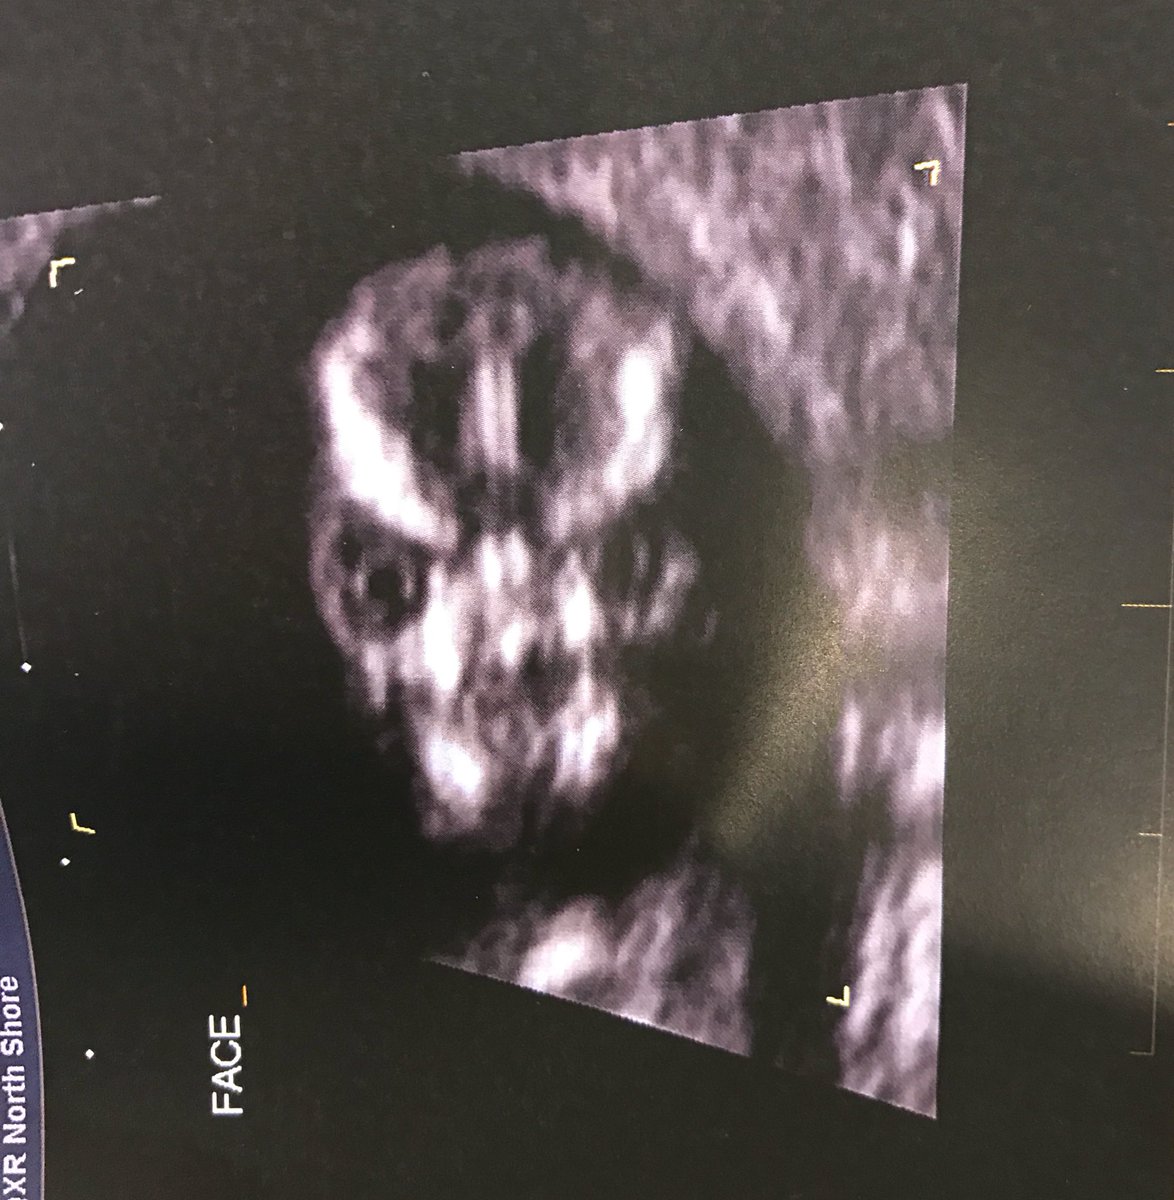

Salah satu yang dilakukannya adalah melakukan pemeriksaan USG. Namun namanya mendadak viral setelah melakukan USG tersebut.

Saat di USG rupanya bayi Sharni sedang tertidur. Namun karena harus dalam keadaan sadar, bayi pun akhirnya dibangunkan.

Namun kejadian setelah itu justru mengejutkan. Ketika wajah bayinya terlihat, calon ibu tersebut pun justru kaget.

Ia mengaku wajah anaknya tersebut sangat menakutkan, terlebih ketika bayi tersebut melotot.

Sharni menganggap anaknya itu tidak suka karena dipaksa bangun. Ia pun membagikan foto USG anaknya lewat akun Twitter pribadinya.

Foto tersebut pun menjadi viral dan mendapatkan share ribuan kali.